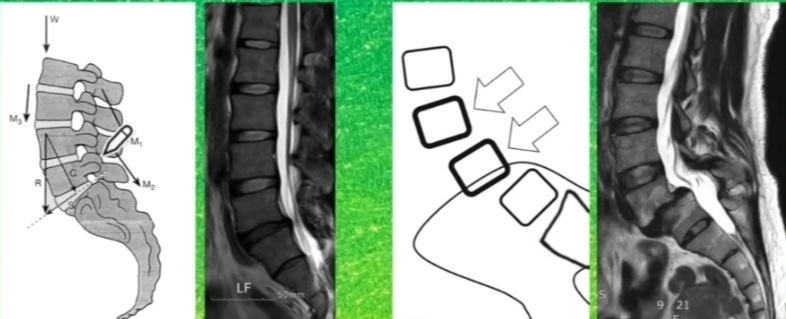

하나의 척추가 인접하는 밑의 척추에 비해 정상적인 정렬을 이루지 못하고 앞으로 빠져있는 상태.

2) 퇴행성 디스크

: 나이가 들면서 디스크 손상으로 척추의 불안정성이 높아지면서 발생